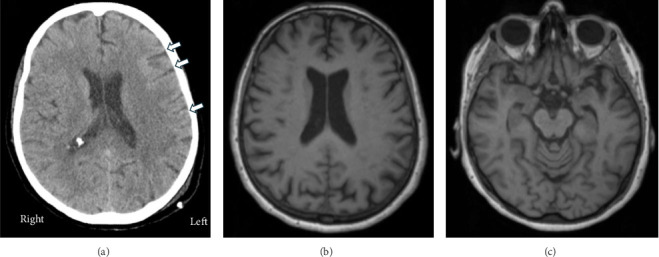

轻度创伤性脑损伤(TBI)后的精神病可能是罕见的、复杂的和功能受损的,通常需要不同专业的投入。这通常需要分开访问和长时间的等待。我们提出的情况下,老年患者精神分裂症样精神病后轻度TBI。创伤性脑损伤三年后,治疗的物理医生要求脑医学诊所(BMC)提供诊断澄清和治疗建议,这是一个由神经病学、精神病学和其他脑相关学科组成的新型综合虚拟诊所。6个月后,患者整体好转,她的驾驶执照在脑损伤后被暂停了6个月,现在又恢复了。我们讨论了TBI的诊断和治疗挑战。bmc可以为复杂脑疾病患者提供及时、全面、高效的多专科护理和资源,最大限度地减少医疗保健中的人工孤岛。

Psychosis after mild traumatic brain injury (TBI) can be rare, complex, and functionally impairing, often requiring inputs from various specialties. This usually entails separate visits and long wait times. We present the case of an elderly patient with schizophrenia-like psychosis after a mild TBI. Three years after the TBI, the treating physiatrist requested diagnostic clarifications and treatment recommendations from a brain medicine clinic (BMC), a novel integrated virtual clinic composed of neurology, psychiatry, and other brain-related disciplines. Six months later, the patient was overall improved, and her driver's license, which had been suspended 6 months after the TBI, was reinstated. We discuss diagnostic and treatment challenges of TBI. BMCs could provide timely, comprehensive, and efficient access to multispecialty care and resources for patients with complex brain disorders and minimize the artificial siloes in healthcare.